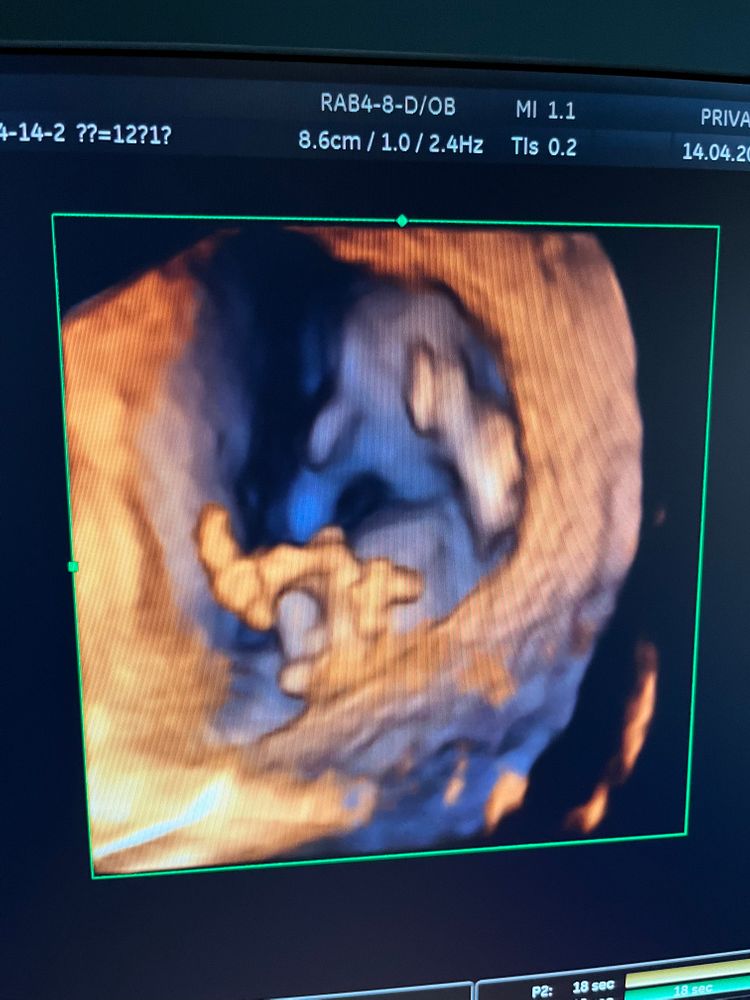

Кто же там мальчик или девочка 🥰

Были на 1 скрининге , врач сказала что видит уже на 80% кто там 🤰 так не терпится узнать. Может кто понимает по фото кто же там)))

На последнем фото если это бугорок, то думаю мальчик . А на УЗИ не сказали кто?